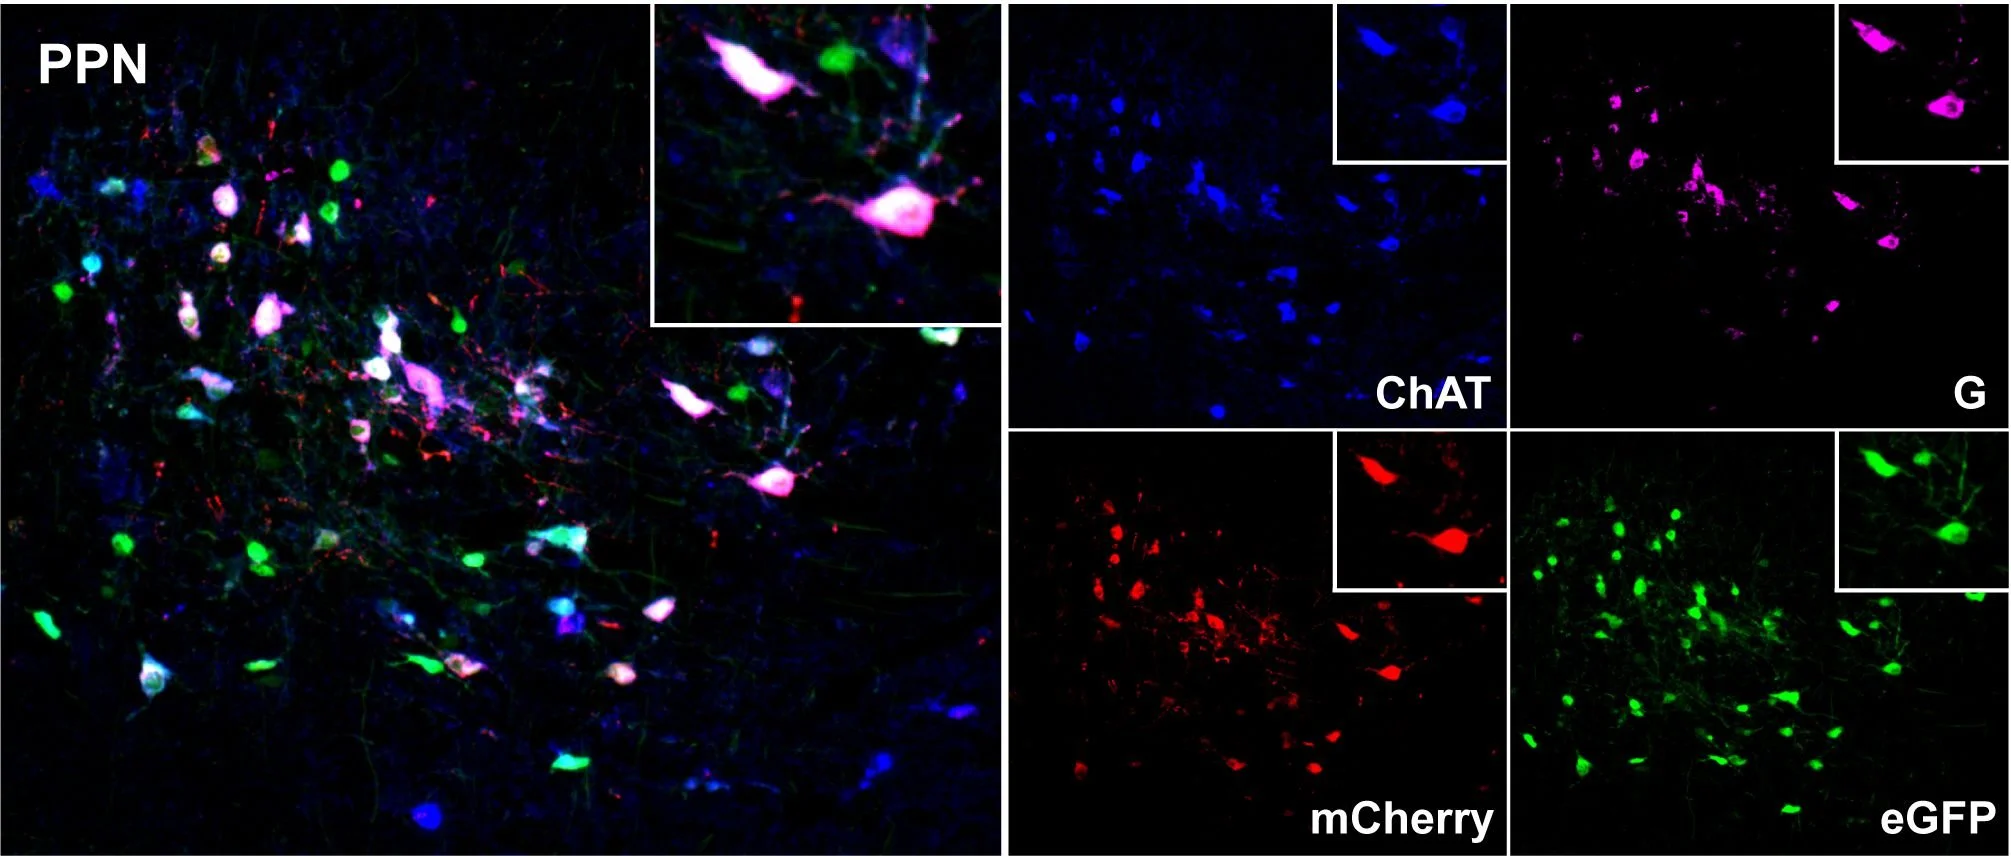

By combining state of the art neuroanatomical tracing with whole-brain pathology mapping techniques scientists at the CNP lab investigate how Parkinson’s disease pathology progresses in the brain. So far, this work has highlighted the importance of cellular vulnerability factors which render certain neurons more vulnerable to the disease process.

Initiating rabies virus tracing in the cholinergic population of the pedunculopontine nucleus.